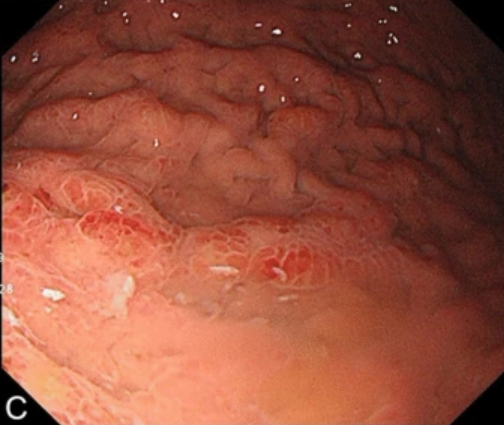

Image of Month: Gastric #cancer metastasis mimicking rectal #IBD This case reminds us to be vigilant about malignancy in IBD. https://t.co/12CuXyVDJc